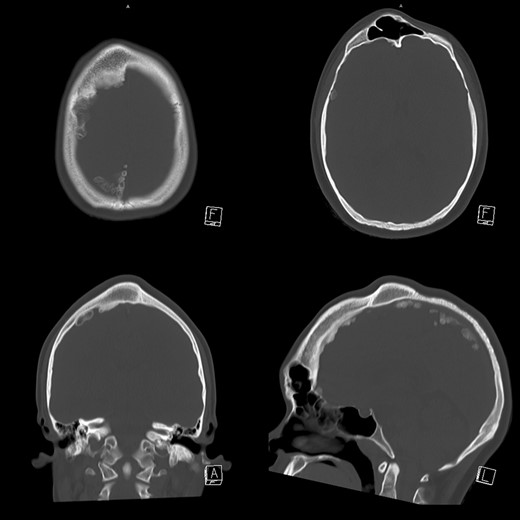

A 17-year-old girl referred to us with a chief complain of a painless bump on her right forehead. She also had a projection on the parietal area. She and her family told that the protrusions had been observed since she was below teenage and had not changed for these 3 years. She had no visual impairment. She felt healthy and self-reported no other abnormality. X-ray computer tomography scan showed osseous hypertrophic lesions in frontal and parietal bone (Figs 1 and 2). Ground glass appearance of diploe implied fibrous dysplasia. Frontal sinus was dilated without mucosal hypertrophy or frontonasal duct stenosis. Multiple intra-cranial calcification was observed. She presented no psychomotor disorder.

Slices of skull CT. Hypertrophy of right frontal and parietal bone is observed. Diploe of the hypertrophic part presented ground glass appearance. Frontal sinus was dilated without mucous hypertrophy. Intra-cranial calcification was also observed.